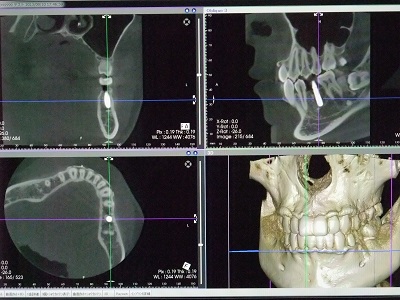

歯科用CTを完備しています。従来の2次元的なレントゲン写真では見えなかったものや見落とされていたものもが3次元的なCTスキャンによって、より正確な診査、診断ができるようになりました。

CTの画面です。

様々な角度から詳細な内部の構造を見ることができます。